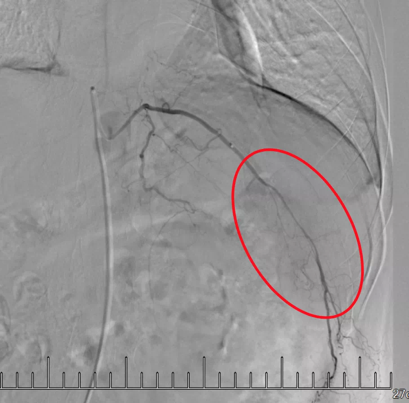

微導(dǎo)管插管到轉(zhuǎn)移瘤所在肋間動脈

造影顯示紅圈內(nèi)“烏云”區(qū)域?yàn)槟[瘤。